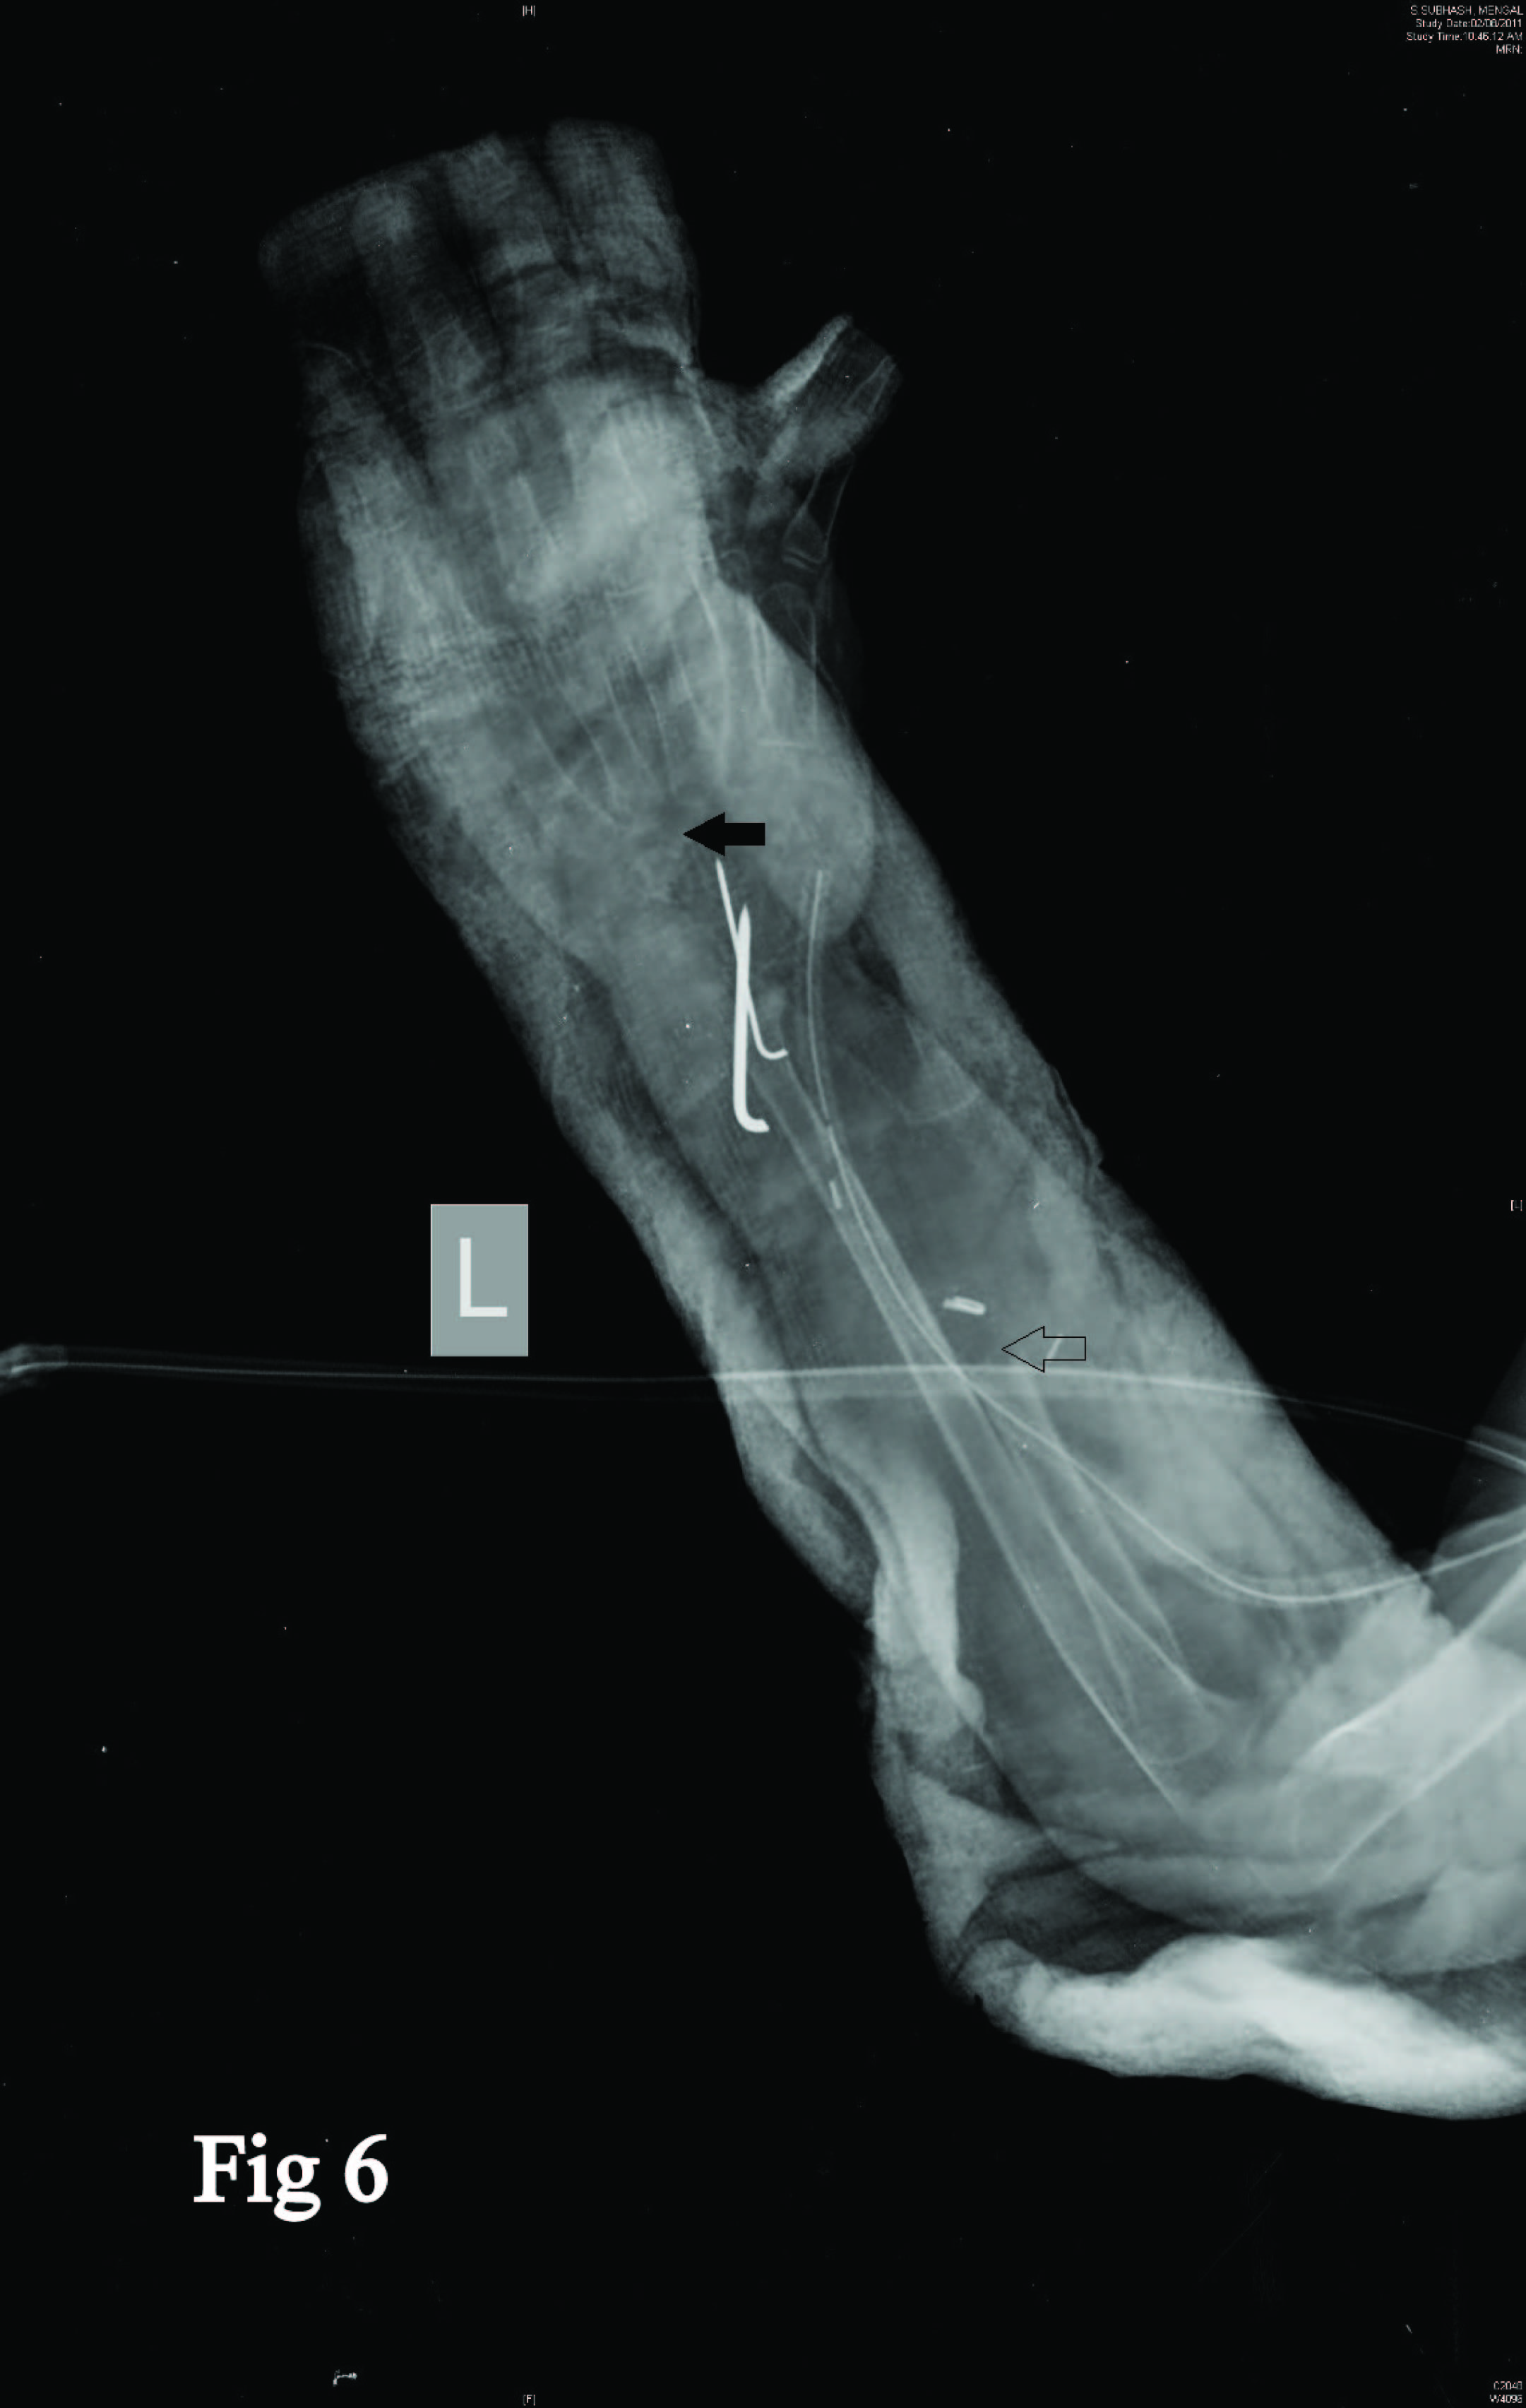

Seven centimeter from articular surface a radial osteotomy was done and specimen delivered [Table/Fig-5]. The carpus was centralized over ulna. Considering the age of the patient it was decided to stabilize the ulnocarpal interface using unthreaded K wires passed through the distal ulna including the distal ulnar physis with a plan to go for ulnocarpal arthrodesis as a definitive procedure at skeletal maturity. Postoperatively the wrist was immobilized in a POP cast for six weeks [Table/Fig-6]. This was followed by a forearm brace immobilization to be continued till skeletal maturity [Table/Fig-7&8]. Supervised regular physiotherapy was recommended to reduce the chance of reflex sympathetic dystrophy.

Postop X-rays showing centralisation of carpus on ulna and ulnocarpal stabilization(solid arrow) with resected radius (arrow)